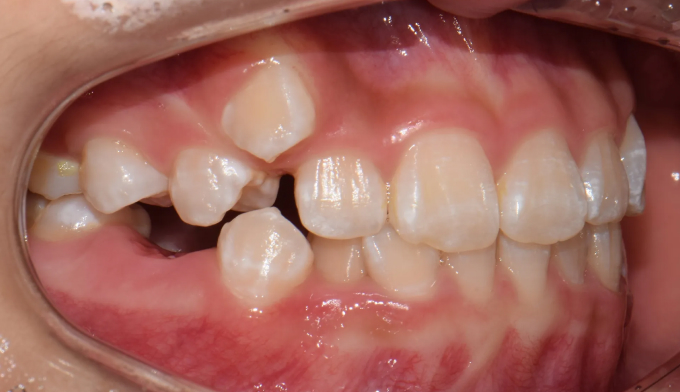

진단해보니 송곳니가 나올 공간이 부족하여 2차교정을 진행하였습니다.

남아있는 공간을 최대한 활용하여 발치없이 치아를 배열해줍니다.